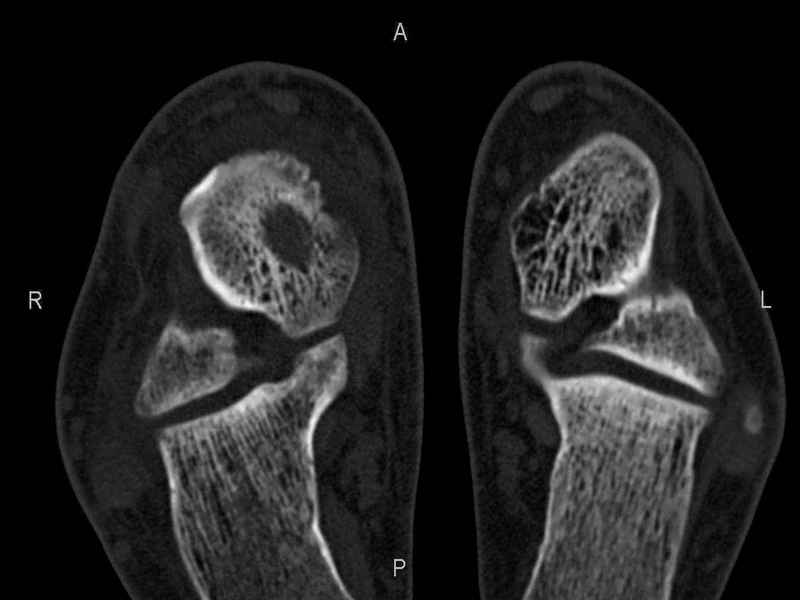

Уважаемые коллеги, обратился за помощью пациент, мужчина, 25 лет. С жалобами на болевой синдром в области голеностопного сустава и среднем отделе стопы. Травму отрицает. Со слов, болевой синдром в течении 1 года. Последние 1-1.5 мес периодически вынужден пользоваться костылями. После ограничения нагрузки боли уменьшаются.Соматически здоров. До появления болей активно занимался рукопашным боем. На СКТ картина рассекающего остеохондрита блока таранной кости, киста шейки таранной кости с признаками импрессии суставной поверхности. А также - разрастания переднего края б\берцовой кости сопровождающиеся клиникой импиджмент синдрома. Предполагаемый план лечения- удаление свободного фрагмента суставного хряща из трансмаллеолярного доступа с рассверливанием поверхности дефекта, кюретаж кисты шейки с заполнением полости биокомпозитом + дебридмент переднего отдела голеностопного сустава. Прошу высказать своё мнение, за и против, предполагаемого плана лечения. А также по возможности ответить на вопросы: 1. Есть ли необходимость в улучшении васкуляризации таранной кости (например подтаранный артродез). 2. Учитывая планируемое применение биокомпозитного цемента целесообразно ли заполнение им дефекта блока таранной кости с моделированием края суставной поверхности.

СТ чётко демонстрирует секвестр, но открыв сустав вероятно, что хрящ тарана окажется интактным и только пальпацией/ ЭОП можно будет

идентифицировать локализацию секвестра. Если вы с этим столкнетесь, то секвестрэктомию я бы предложил сделать не со стороны суставной поверхности тарана, а со стороны угла тарана, субхондрально кюрретаж стенок, разнонаправленную туннелизацию спицей или 1.1мм сверлом и заполнить дефект спонгиозным графтом.

- киста шейки тарана, как вы думаете, какова её природа : аваскулярный некроз? эхинококк?